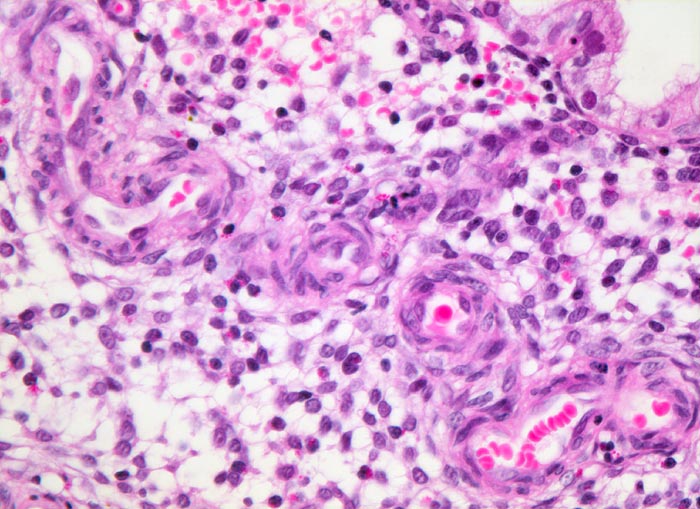

• Tumorzellverbände infiltrieren die glatte Muskulatur des Myometriums.

• Tumordrüsen ausgekleidet von mehrreihig angeordneten Tumorzellen mit hyperchromatischen polymorphen längsovalen Tumorzellkernen mit zahlreichen Mitosen. Die Morphologie der Tumordrüsen erinnert an proliferatives Endometrium.